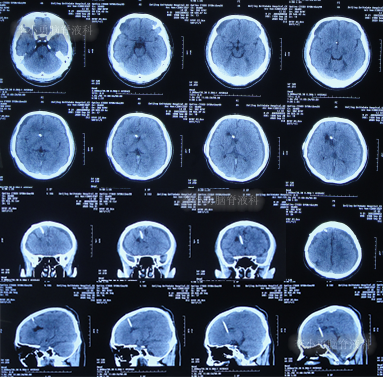

发现脑积水15年后即2020年1月份,开始出现头胀头闷能自行缓解,并没有特殊处理,3月后即2020年4月8日,因症状变重且变频繁,至甘肃省天水市某医院检查头颅核磁(图-3)认为脑积水较前(2016年7月20日头颅CT)加重。

图-3:2020年4月8日头颅核磁

1个月后即2020年5月6日,为治疗脑积水,至陕西省西安市某三甲医院就诊,查头颅核磁示脑积水(图-4)。

图-4:2020年5月6日头颅核磁